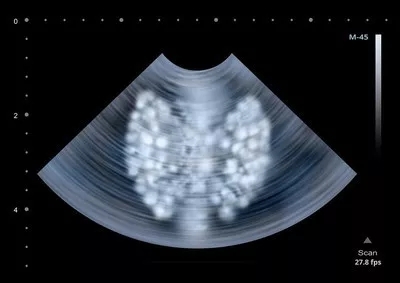

DTC发生肺部转移的胸部CT检查特征,主要分为(1)单发肺部结节(孤立);(2)多发肺小结节(直接≤1cm);(3)多发肺大结节;(4)双肺弥漫性转移灶。

(4)双肺弥漫性转移者,经过多次碘131治疗后,可能导致肺纤维化和放射性肺炎并发症,应该注意控制碘131给药剂量。